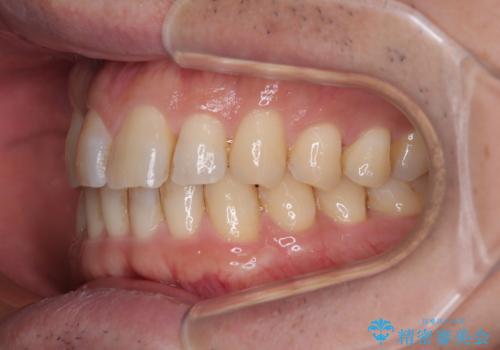

- クリアブラケット

- 1年1ヶ月

- 上下前歯のデコボコを気にして来院された患者様です。

ワイヤー矯正でもマウスピース矯正でも可能でしたが、短期間で、自身の手を煩わせることなく治療を行いたいとのことで、ワイヤー装置にて矯正治療を行うこととしました。

上顎前歯の舌側転位が顕著であったため、治療期間が長くなると思われましたが、僅か1年で無事に終えることができました。